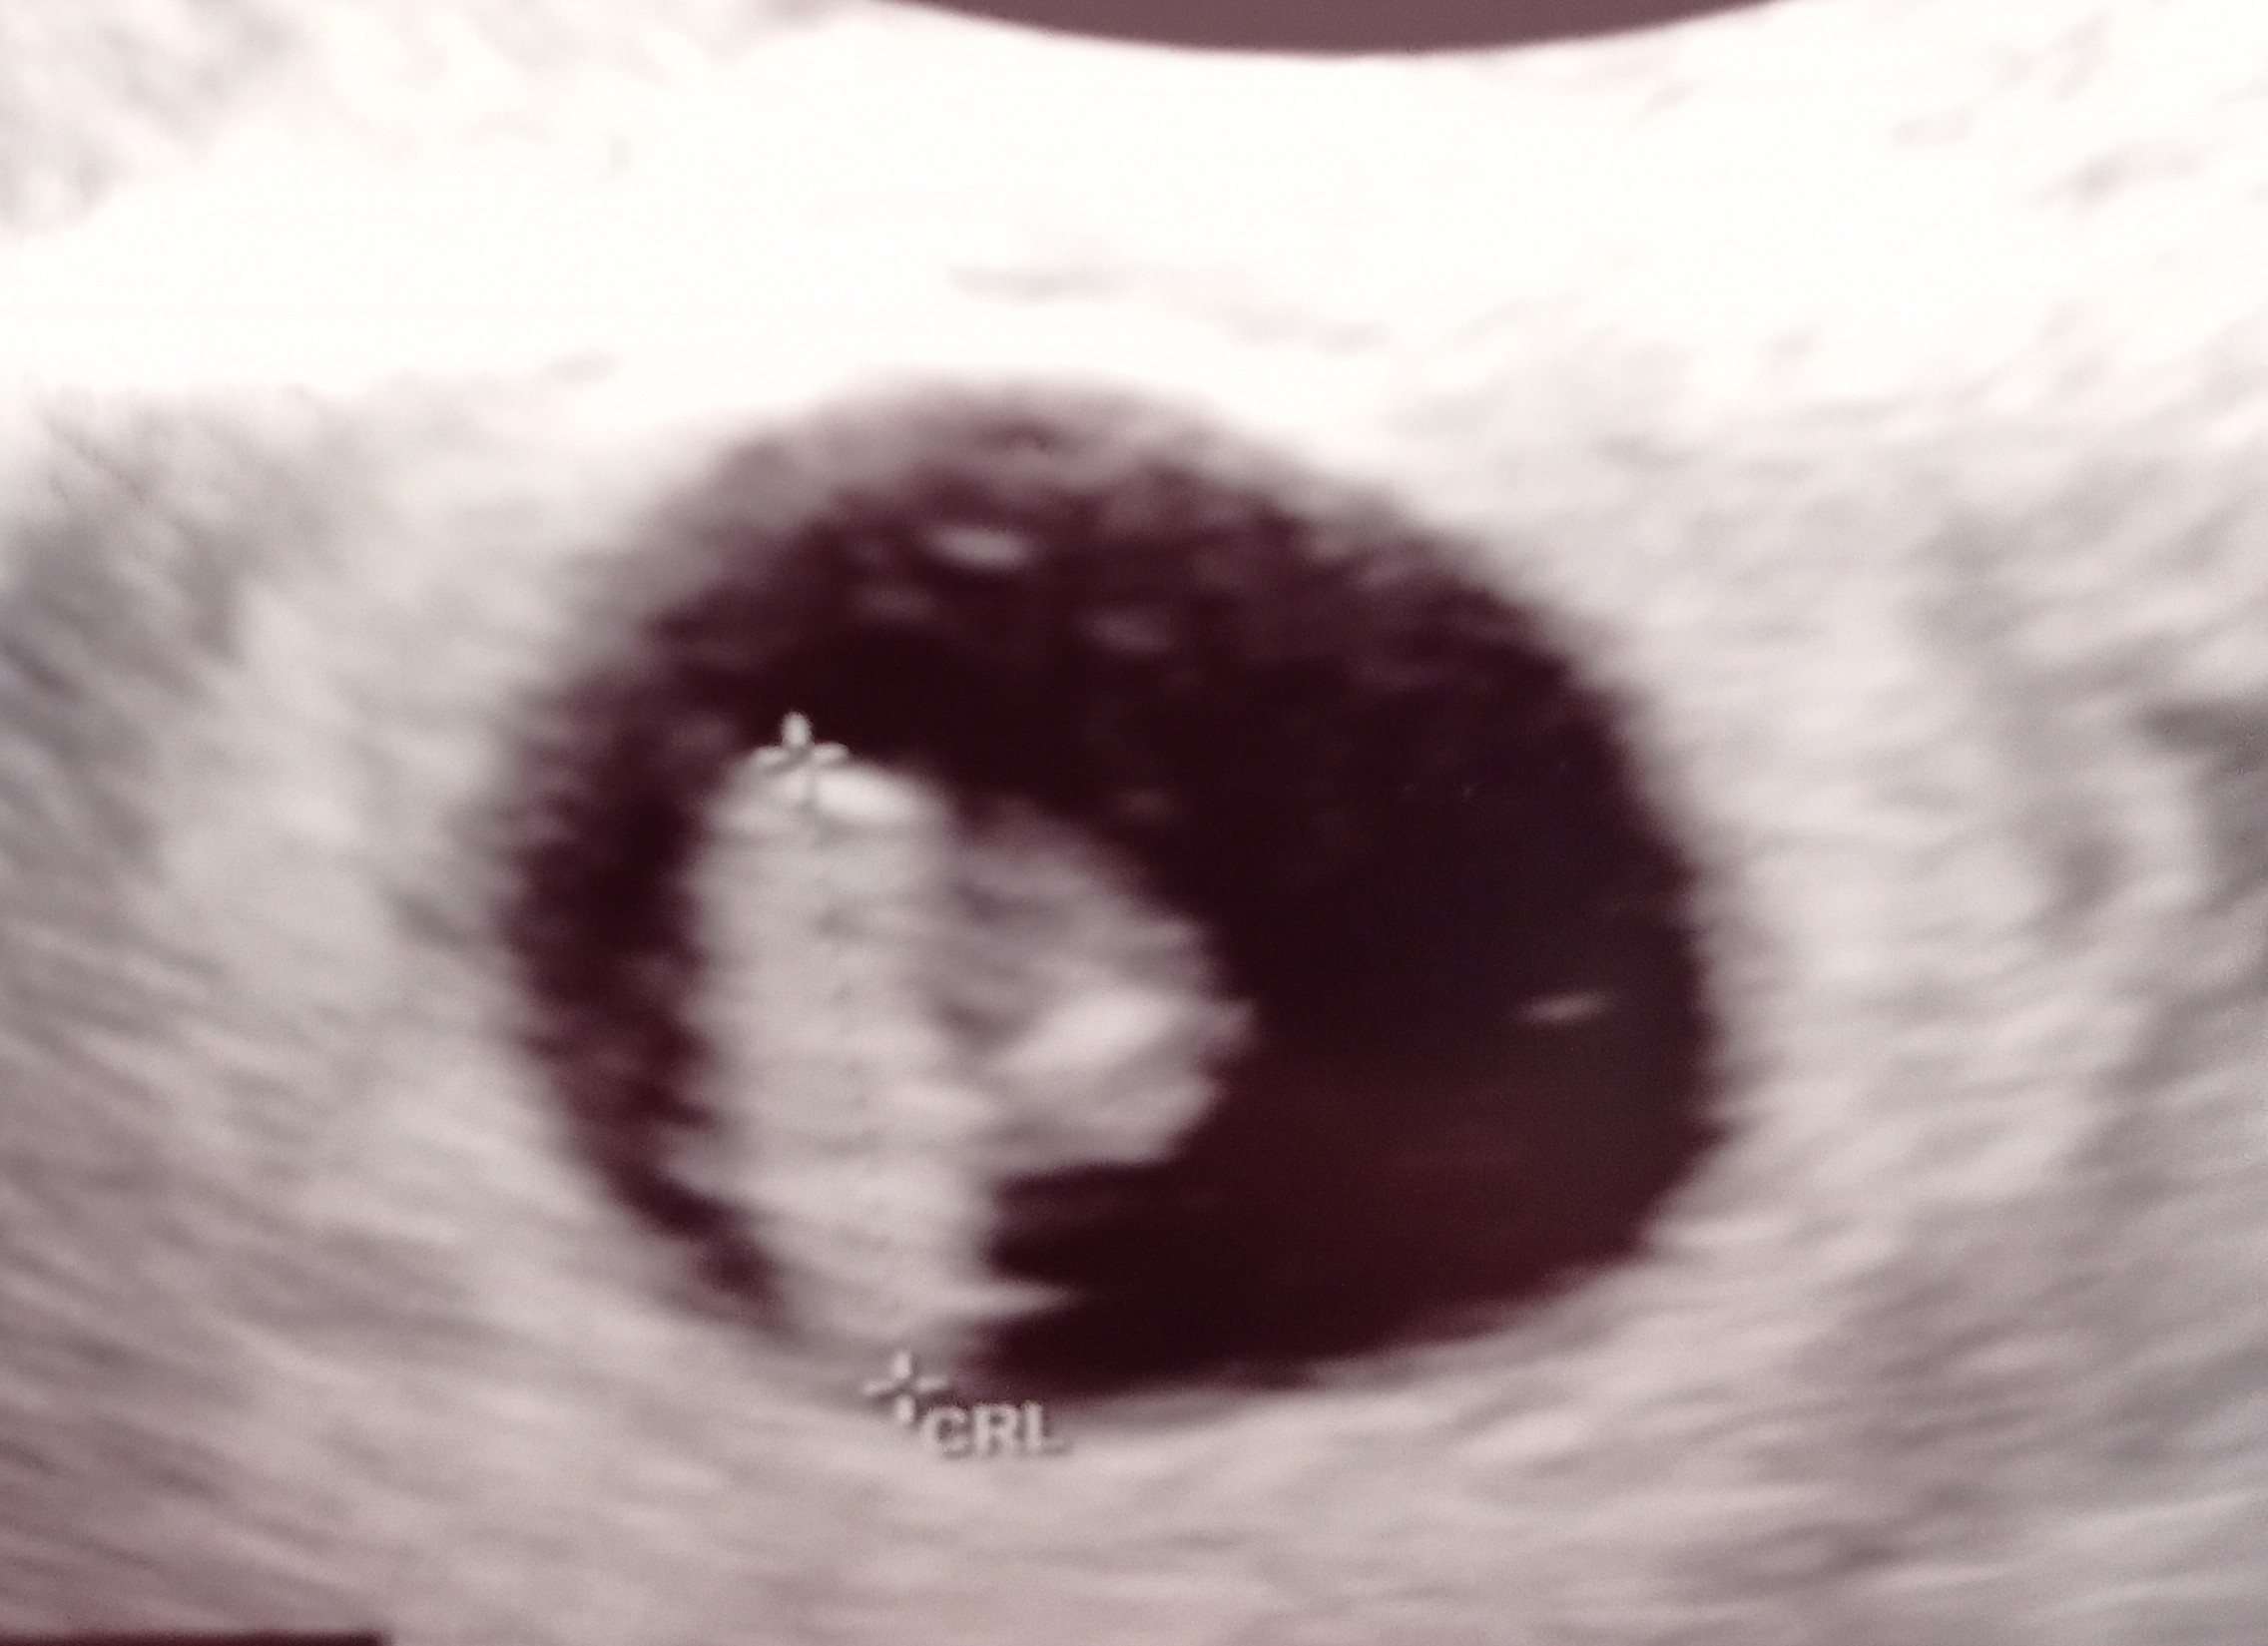

bardzo się cieszę! Nie chce wiedzieć co przeżyłaś przez ta noc. Na szczęście to tylko błąd lekarza.Dziewczyny, jestem już po. Maluch ma 1.1cm, rośnie prawidłowo. Wczoraj lekarz źle zmierzył i doprawił tyle stresu

Wiedziałam!Dziewczyny, jestem już po. Maluch ma 1.1cm, rośnie prawidłowo. Wczoraj lekarz źle zmierzył i doprawił tyle stresu

superDziewczyny, jestem już po. Maluch ma 1.1cm, rośnie prawidłowo. Wczoraj lekarz źle zmierzył i doprawił tyle stresu

Cudowna wiadomość! Bardzo się cieszę :-) Zrelaksuj się teraz, bo miałaś ogromny stres.Dziewczyny, jestem już po. Maluch ma 1.1cm, rośnie prawidłowo. Wczoraj lekarz źle zmierzył i doprawił tyle stresu

CudownieDziewczyny, jestem już po. Maluch ma 1.1cm, rośnie prawidłowo. Wczoraj lekarz źle zmierzył i doprawił tyle stresu